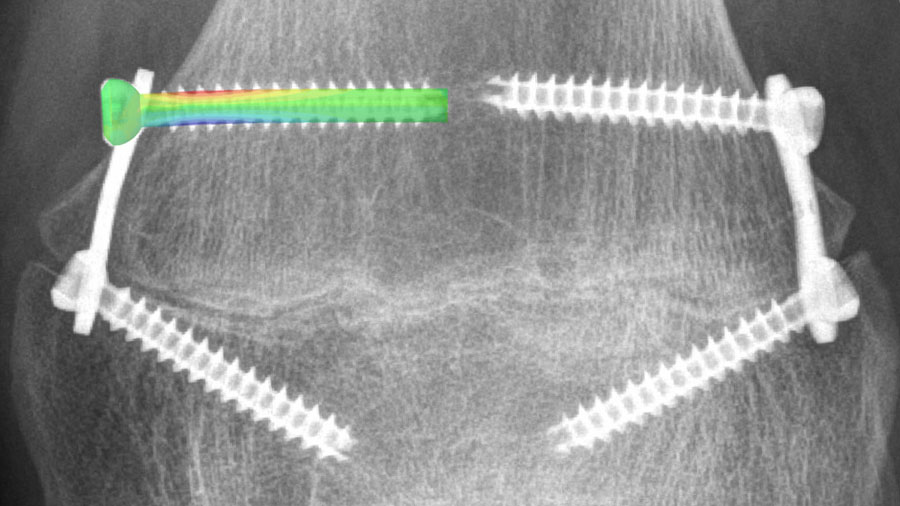

Radiograph of distal femur with two plates for epiphysiodesis, superimposed with illustration of the resulting strains in one of the deformed screws during management of leg length discrepancy in children and adolescents